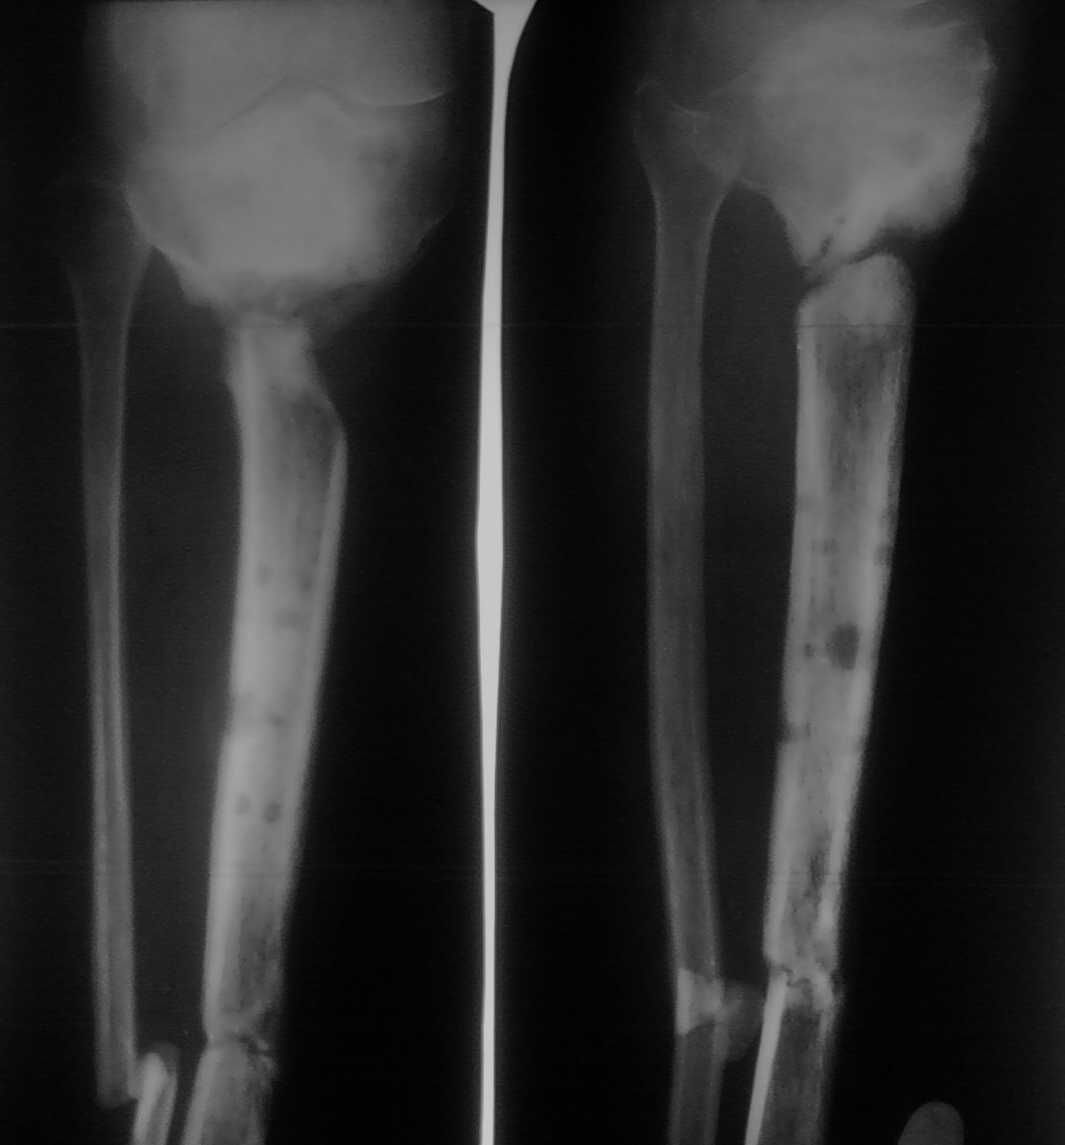

Уважаемые коллеги!Помогите определиться с тактикой лечения пациента с застарелым

переломом голени

Больной лечится уже год. Первоначально был открытый перелом дистальной части костей голени

и закрытый - в проксимальной части большеберцовой кости. Больного вели на аппарате внешней

фиксации. Результат - на снимке. Какую тактику лучше избрать в данном случае?